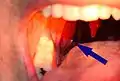

حصاة بارزة من اللوزة

حصاة كبيرة يظهر نصفها من اللوزة